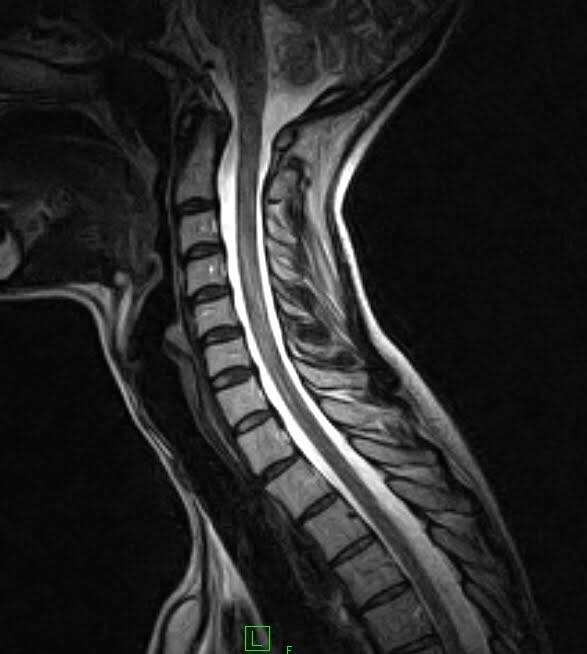

Neurologie is de medische tak die zich bezighoudt met ziekten en aandoeningen van het zenuwstelsel. Dit omvat problemen met de hersenen, het ruggenmerg, het hersenvocht, de perifere zenuwen en spieren.